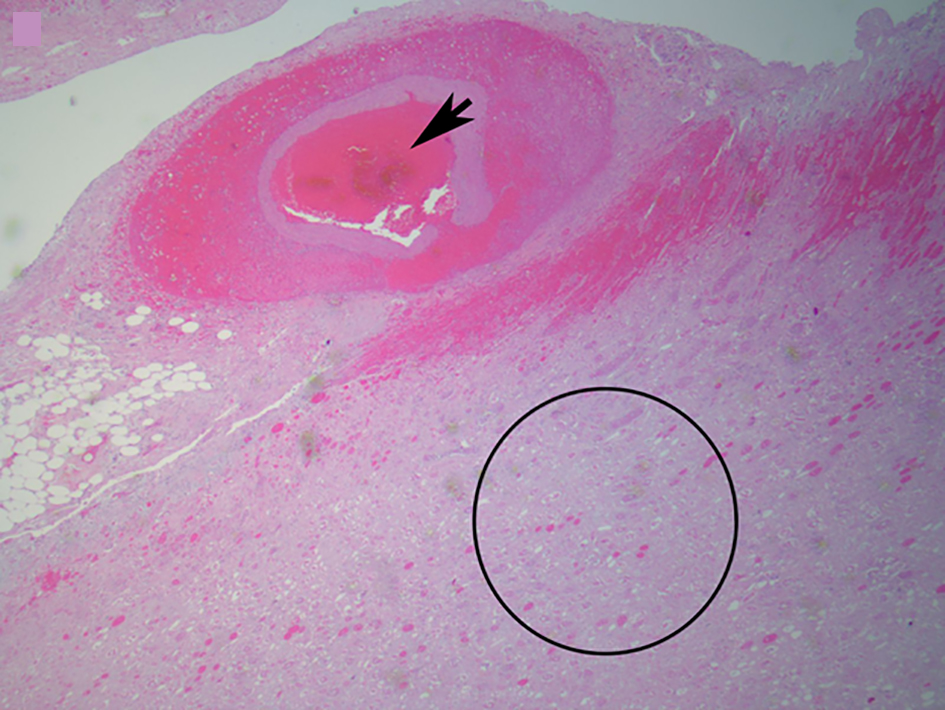

The abdominal aorta gives rise to the renal arteries at the levels of L1-L2. In the majority of individuals, the renal artery gives off branches that become the anterior and posterior divisions, and inside the hilum the anterior renal artery will give rise to the apical, anterior and inferior segmental branches. The segmental vessels branch deeper into the renal parenchyma to finally reach the capillaries and glomeruli [4] (Fig. 2). It is in fact believed that the renal circulation is the final resting place for up to 2.3% of systemic arterial embolizations [5] (Figs. 3-5).

![]() Click for large image | Figure 5. Microscopic image of an arterial thrombus showing a vessel completely occluded by the thrombus (black arrow) and the resulting renal infarct (in and around circle) (from Fig. 4) (H&E, × 2.5). |